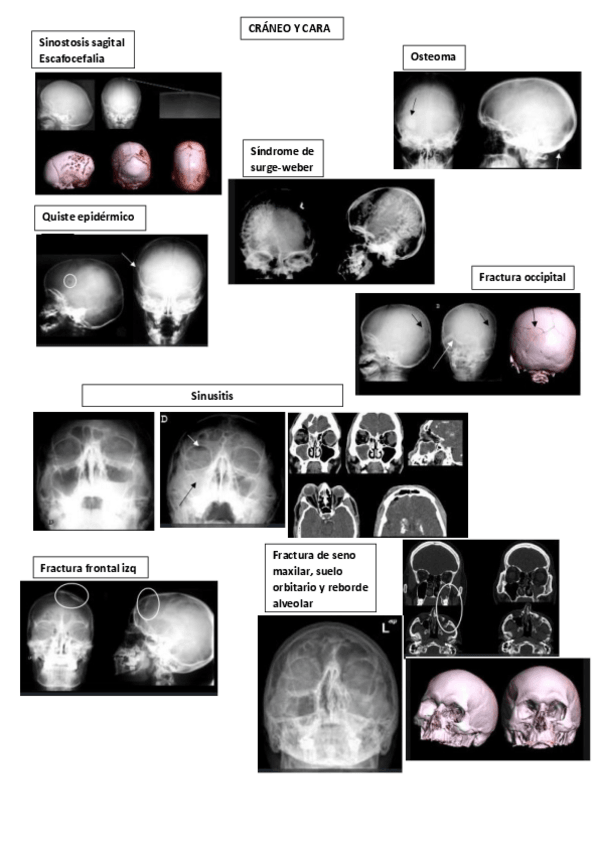

Ejemplos de RX, TC, RM de las enfermedades que hemos visto en clase o en prácticas. NO son fotos de clase ni de prácticas

practicas-de-Rx-simple-craneo-ycara.pdf